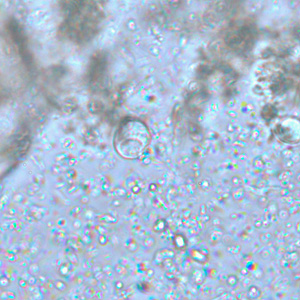

E. histolytica trophozoite

single nucleus with centrally placed karyosome. Cytoplasm contains ingested RBC’s.